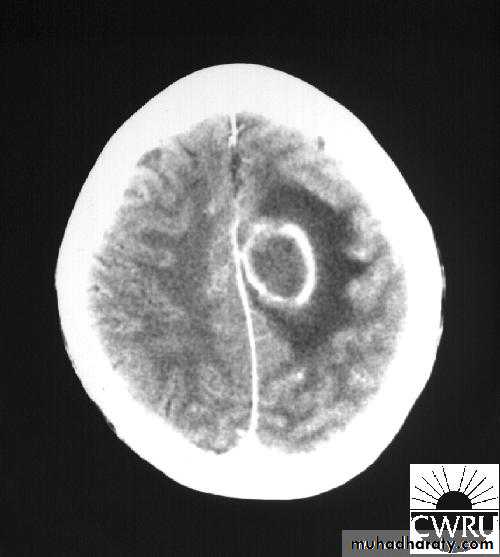

Brain Abscess CT with contrast

Neurosurgery

• CT or MRI is the investigation of choice.

• CT Brain is performed with and without contrast.

• MRI is done with gadolinium enhancement.

• They will show a single (or multiple) space occupying lesion that is well delineated with an enhancing wall, with variable surrounding oedema.